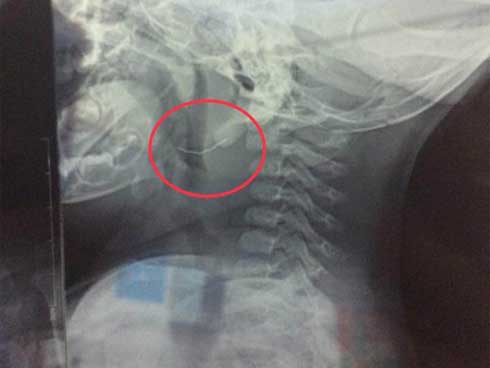

Mẩu bút chì nguyên nhân gây tắc nghẽn đường thở khiến bé ngưng tìm, ngừng thở

Kíp mổ do BS. CKII Đinh Xuân Hương – Phó giám đốc Bệnh viện kiêm Trưởng khoa Tai Mũi Họng, và BS.CKI Đoàn Nhân Chính - Phó khoa Tai Mũi Họng, Bệnh viện Sản Nhi Nghệ An trực tiếp mổ, sau hơn 1h căng thẳng, kíp mổ đã gắp ra được dị vật trong phế quản của bệnh nhân là đầu bút chì có đường kính 2cm, giành lại sự sống cho bệnh nhân.